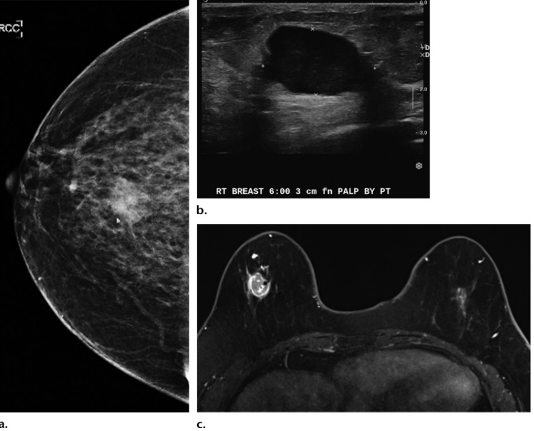

Carcinoma ductal invasivo (IDC) em mulher de 59 anos com síndrome de Lynch. (a) Mamografia craniocaudal (CC): massa espiculada na mama direita, às 6 horas. (b) Ultrassonografia direcionada: massa hipoecoica irregular, medindo até 2,6 cm (palpável pela paciente). (c) Ressonância magnética axial: massa solitária heterogeneamente realçada no quadrante ínfero-interno da mama direita. Biópsia: confirmou carcinoma ductal invasivo triplo-negativo (IDC).